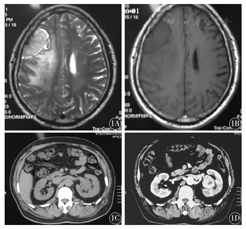

例1,男性,67岁。2012年当地体检胸腹部CT示左肾占位,当时无尿频、尿急、尿痛、腰痛、血尿等症状,未予重视。2015年4月下旬起患者出现左下肢无力,并逐渐加重,偶有头晕。2015年6月初当地医院头颅磁共振成像(MRI)示:右侧额叶占位灶(图1A、图1B)。2015年6月中旬腹部CT示:左肾肾盂处占位性病灶(图1C、图1D)。入院后予脱水等对症处理,但患者左下肢无力仍逐渐加重,左下肢肌力下降(Ⅳ+)。2015年6月19日在全身麻醉下行"右侧额叶占位切除术" 。病理:血管母细胞瘤[世界卫生组织(WHO)Ⅰ级]。免疫组织化学:VHL+++,血管内皮生长因子受体(EGFR)+++,CD10-,CK7-,CD117-,HMB-45-,Melan-A-,CA-9-,Ki-67+ 5 %。网状纤维染色(-)。2015年7月8日在腹腔镜下行"根治性左肾及肾盂切除术" ,病理示:左肾透明细胞癌(Ⅱ级),肾包膜、输尿管切端未见癌组织累及。该患者为右侧额叶血管母细胞瘤及肾透明细胞癌(VHL 1型),目前无肢体活动障碍,无视力视野改变,无血尿、腰痛不适,仍在随访中。

1A:颅脑MRI示右额叶T2WI以长T2为主的信号区;1B:MRI示右额叶T1WI等信号区;1C:CT示左肾肾盂占位;1D:CT示左肾肾盂占位较前增大,增强动脉期呈均匀性强化